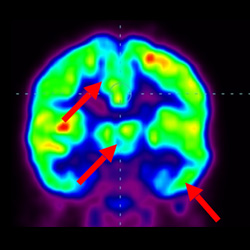

細(xì)胞治療前 PET CT 掃描顯示神經(jīng)組織中的藍(lán)/黑色區(qū)域,表明腦癱引起的大腦損傷。

腦癱細(xì)胞療法, 腦癱治療

細(xì)胞治療后,藍(lán)色和黑色區(qū)域減少,并且看到更活躍的區(qū)域。這表明損傷減少并改善了大腦功能。